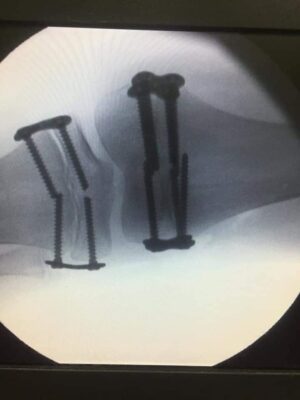

У Львові ортопеди провели сучасну операцію та виправили вкорочення ніжки на 3,5 см у 9-річної дівчинки з ДЦП. Про це повідомляють на сторінці у Facebook Львівського ОХМАТДИТУ. Віка приїхала до Львівського ОХМАТДИТу з Чернівців. У неї - ДЦП, правобічний геміпарез, а ще права ніжка була коротшою від лівої аж на 3,5 см. Дівчинці було важко ходити, вона вже помітно кульгала. Ортопеди виправили її проблему сучасним малоінвазивним способом. У львівському ОХМАТДИТі роблять сучасну ефективну операцію: тимчасове блокування зон росту іншої ніжки спеціальними імплантатами. Це такий сучасний спосіб, коли одна ніжка тимчасово перестає рости, "чекає", доки підтягнеться інша до її рівня, а потім, коли дві ніжки однакової довжини, лікарі видаляють імпланти.

«Менша ніжка підросте, ми знімемо пластину і за деякий час чекаємо врівноваження довжини обох ніжок і в дівчинки покращиться хода, вона перестане кульгати», - пояснює завідувачка ортопедичного відділення Злата Кузьо.

Такі операції в ОХМАТДИТі роблять малотравматичним способом, без гіпсу і допоміжних засобів, тож дитина за день-два повертається до звичного життя - ходить, бігає, згинає ногу тощо. На другий день Віка уже поїхала додому. Команда Супергероїв в операційній: ортопеди Олександр Корольков, Злата Кузьо, Оксана Колодій, хірург-інтерн Назар Росоловский, анестезіолог - Мар'яна Собко, операційна медсестра - Тетяна Качмарик, анестезистка - Наталя Голинська і молодша медсестра - Світлана Мєскало.